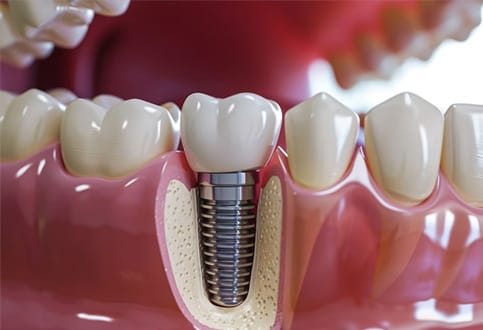

Trồng răng Implant là giải pháp phục hồi răng mất hiện đại, mang lại khả năng ăn nhai gần như răng thật và độ bền lâu dài. Tuy nhiên, một trong những câu hỏi được quan tâm nhiều nhất là: Giá trồng răng Implant tại TP.HCM bao nhiêu?